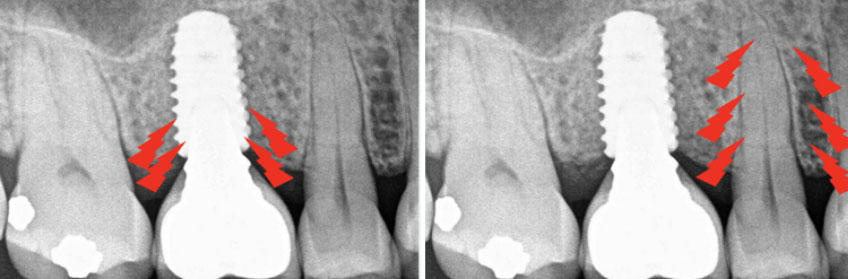

In addition, the PDL offers additional protection by absorbing pressure when heavy occlusal forces are applied to the tooth. A natural tooth can be displaced 25–100 µm in the axial direction and 56–108 µm horizontally, compared with a dental implant, which can only be displaced 3–5 µm axially and 10–50 µm horizontally. The PDL also allows the tooth to adapt to excessive forces through intrusion or rotation and by distributing the load along the entire root surface. In contrast, because a dental implant is connected directly to the bone, it does not have the same adaptive capabilities. Thus, if an implant is subjected to similar forces, the load is concentrated at the crestal bone, increasing the susceptibility to irreversible bone loss.

When delivering an implant restoration, the restoring dentist must recognize the physiologic differences between a dental implant, a natural tooth, and the surrounding bone. Because a dental implant cannot adapt under heavy occlusal forces, it will be introduced to premature contacts when the tooth-borne and implant restoration are adjusted similarly. A mutually protected occlusal scheme will protect the implant in vertical and lateral movements to avoid the negative consequences of early contact with the dental implant.